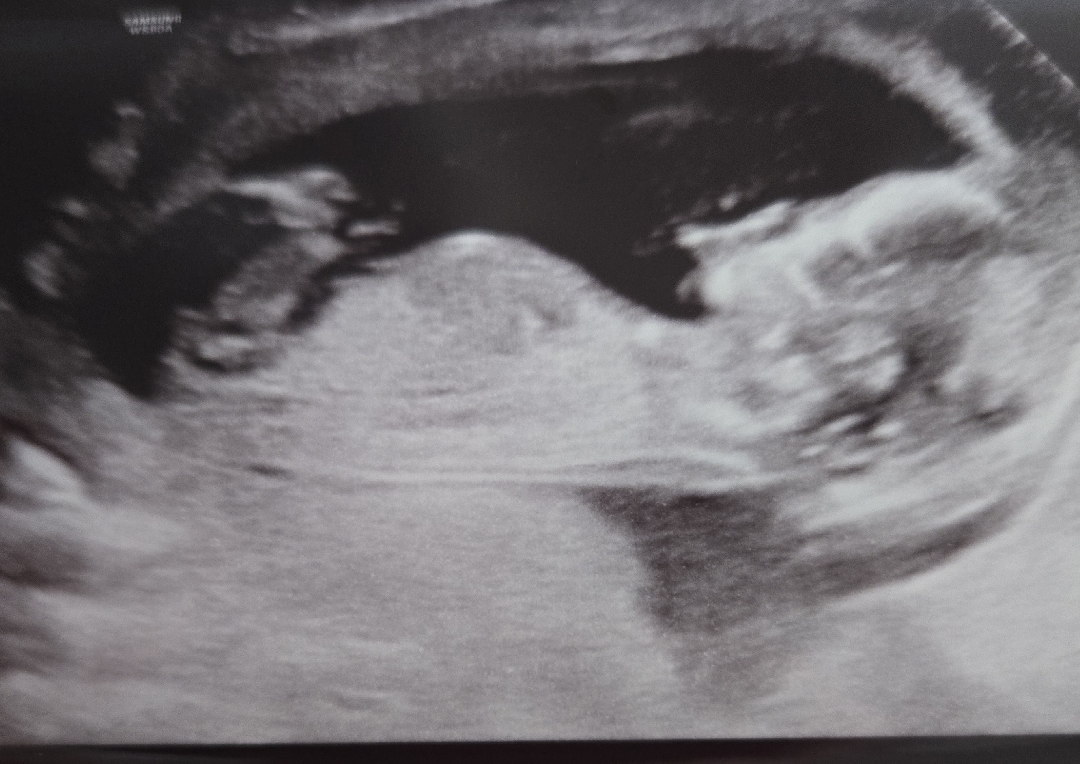

각도법 봐주세요~ㅋㅋ

오늘 검사하고 의사쌤이 이 상태로 없어지면 딸일거라고 두고보자하셨는데 어때 보이나요?

돌기가 잘 안보이네요. 원장님이 딸이라고 하시면 맞겠죠?! 🙏